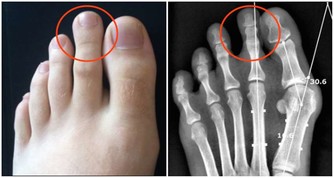

拇指腫脹呈鼓槌狀:容易患先天性心髒病或支氣管擴張等胸部疾病。

小指短小:提示生育機能弱,腎氣不足,易患頭暈、耳鳴、腰腿酸痛等病。